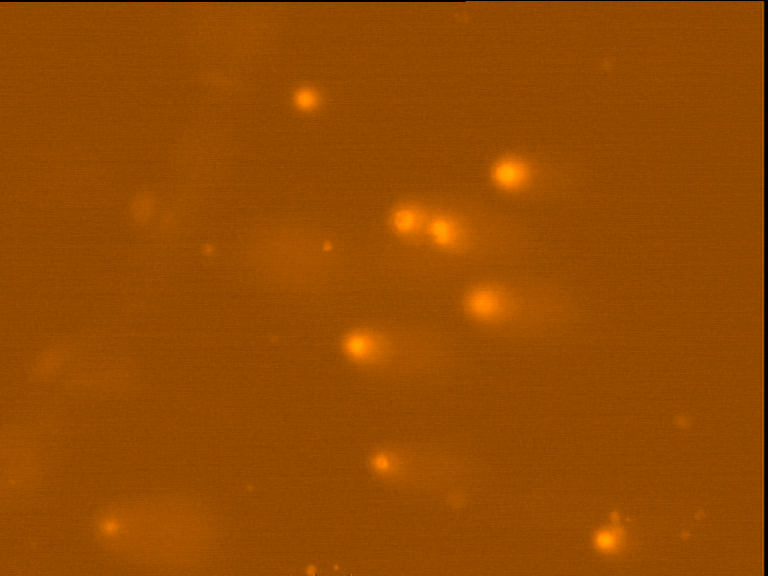

Fig. 4 through 6 show the morphological features of Raji cell sub-lines exposed to DOX, indomethacin, or verapamil. Some of the reversal agents significantly increased the frequency of apoptotic cells compared with control cells. Thus, the P-gp reversal agents were able to overcome apoptotic resistance in the NHL cell-line model. Apoptotic cells in the controls contributed approximately 10% of the whole population (i. e., 61/600 x 100 = 10.16% for TK+ and 69/600 x 100 = 11.5% for TK-). After exposure to the P-gp reversal agents, apoptic cells increased to 22.3% with indomethacin and to 43% with doxorubicin in TK+ cells. In TK- cells, apoptic cells increased from 11.5% to 26.8% and 75.7% with indomethacin and doxorubicin, respectively.

Fig. 5: Morphological features of Raji TK+ cells after treatment with indomethacin (1), verapamil (2) and DOX (3). In each row, left images show intact cells, middle images show apoptotic cells, and right images show necrotic cells as they appeared under the microscope X 200

Fig. 6: Morphological features of Raji TK- cells after treatment with indomethacin (1), verapamil (2), and DOX (3). In each row, left images show intact cells, middle images show apoptotic cells, and right images show necrotic cells as they appeared under the microscope X 200